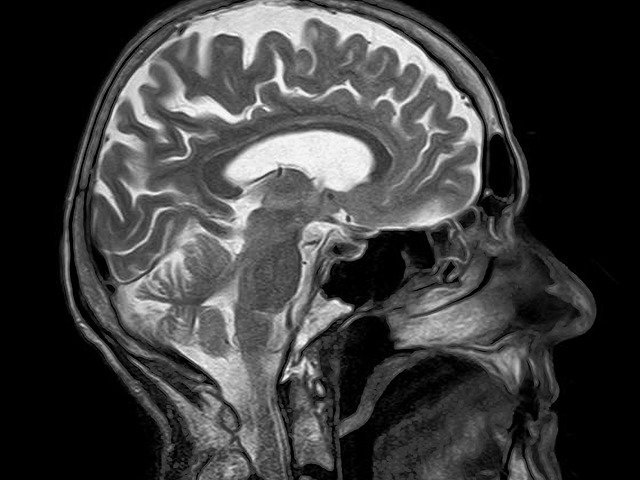

엠알아이, MRI, 에마라이 등 병원에 가면 자주 쓰는 말이긴 하지만 정작 무슨 뜻인지는 모르고 쓰는 경우 많지요? 당연히 영어의 약자를 따와서 MRI라고 부릅니다. 풀네임으로는 Magnetic Resonance Imaging입니다. 우리말로 하면 자기공명영상장치.

MRI (Magnetic Resonance Imaging) - 자기공명영상장치 또는 자기공명영상법

자력에 의하여 발생하는 자기장을 이용하여 생체의 임의의 단층상을 얻을 수 있는 첨단의학기계, 또는 그 기계로 만든 영상법